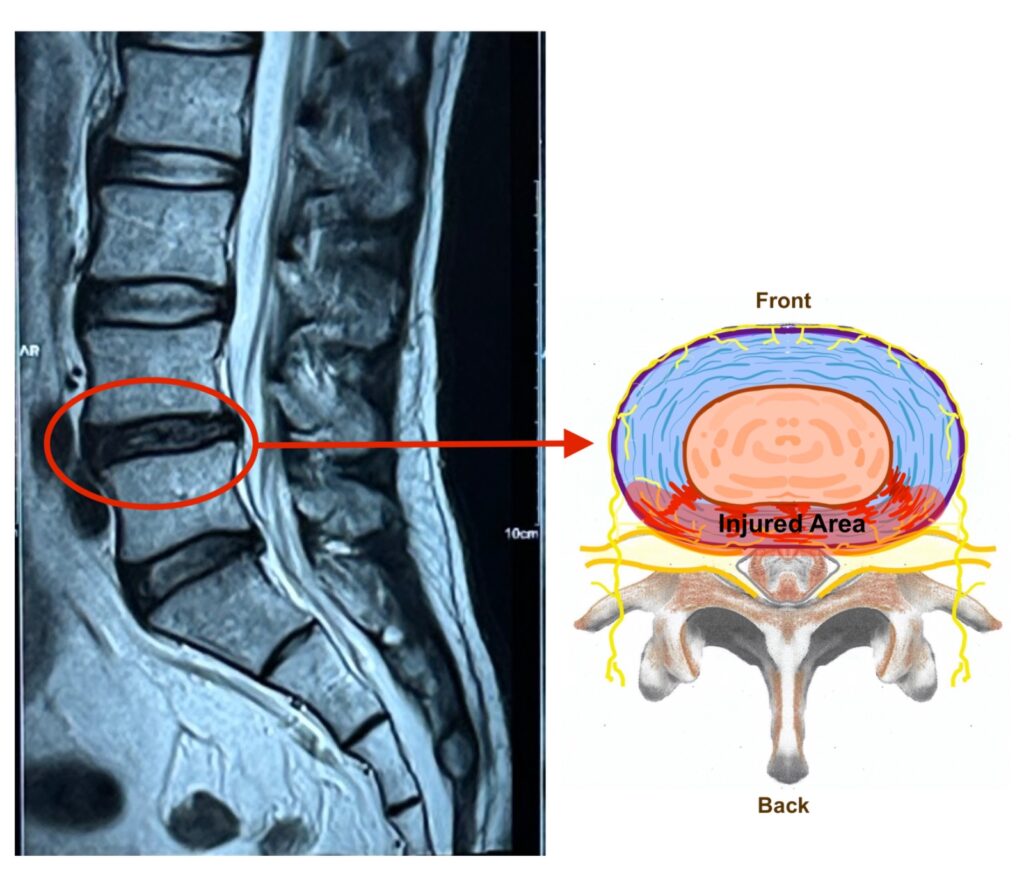

2. Lumbar Discogenic Pain

Each of the vertebrae is cushioned with a disc. The lumbar intervertebral disc functions as an absorber to the intense pressure bore by the vertebrae. Within inside the disc, there are fine nerve fibers which relay pain signal when the disc is injured. Patients with this condition will have difficulty sitting or standing for a longer period. They may experience low back pain when abdomen pressure is exerted on to the disc, during coughing or sneezing. The MRI usually have findings such as ‘annular tear’, mild disc herniation and black disc.